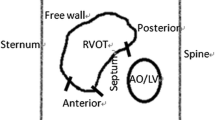

The procedure for Micra™ deployment has been well described before [10]. Briefly, patients were placed in a supine position and local anesthesia was administered at the right inguinal area. The femoral vein was punctured using the modified Seldinger technique and the Micra™ delivery catheter (Medtronic, Minneapolis, MN, USA) was inserted into the inferior right atrium via the IVC. The delivery catheter through the sheath was bent to cross over the tricuspid valve annulus to the right ventricle (RV). In the radiography group, the RV septum was visualized via the precise right ventriculography by the operator and the Micra™ was subsequently implanted in the mid-septum. The specific implantation steps are described below: a pigtail catheter (6Fr; TERUMO, Kyoto, Japan) was delivered along a sheath to the apex of the right ventricle, and the right ventriculography was achieved by injection of 20 cc contrast under fluoroscopic views in the right anterior oblique (RAO) 30° ± 10° and left anterior oblique (LAO) 45° ± 10° positions, respectively (Supplemental Materials Figure S1). The right ventriculography under fluoroscopic RAO30 showed the RV septum that was divided into nine subdivisions (named zones 1–9, Fig. 1A) and zone 2 (the mid-septum) was chosen as the initial intended implantation site for deployment of the Micra™ (Fig. 1C). In the non-radiography group, regular cap injection of 10 mL contrast was conducted that usually showed a small region of the right ventricle (Supplemental Materials Figure S1). In both groups, after transvalvular access to the right ventricle, the Micra was slightly rotated clockwise to point to the intended area in the fluoroscopic image of RAO 30, and the Micra™ was subsequently adjusted clockwise at the LAO view (usually at 40°). This was performed to ensure that the angle between the Micra™ and the spinal vertebrates was 70 to 90° and the height of the Micra™ was adjusted according to the spinal vertebrate positioning, which aided the anchoring of the Micra™ to the median septum.

Right ventriculography under fluoroscopic RAO30 (A, B, and C) and LAO45 (D) in a patient. Nine septal subdivisions are depicted in the RAO30 image (A) following contrast injection that shows the RV septum (B). LAO45 (D) shows the separation (the green line) between RV and LV. The delivery catheter with Micra™ is shown in C and D